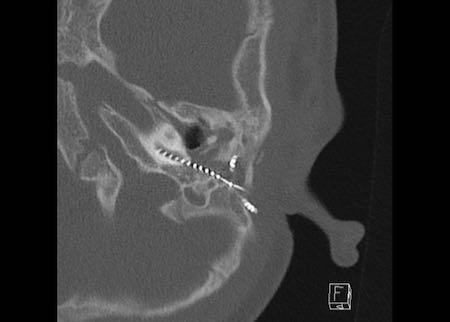

Ca lâm sàng 1

Các hình ảnh cho thấy tai trái của cùng bệnh nhân, nơi thính lực bị suy giảm.

Điện cực không được đưa vào đủ sâu, năm kênh nằm trong hòm nhĩ và đầu điện cực không đạt tới đỉnh ốc tai.